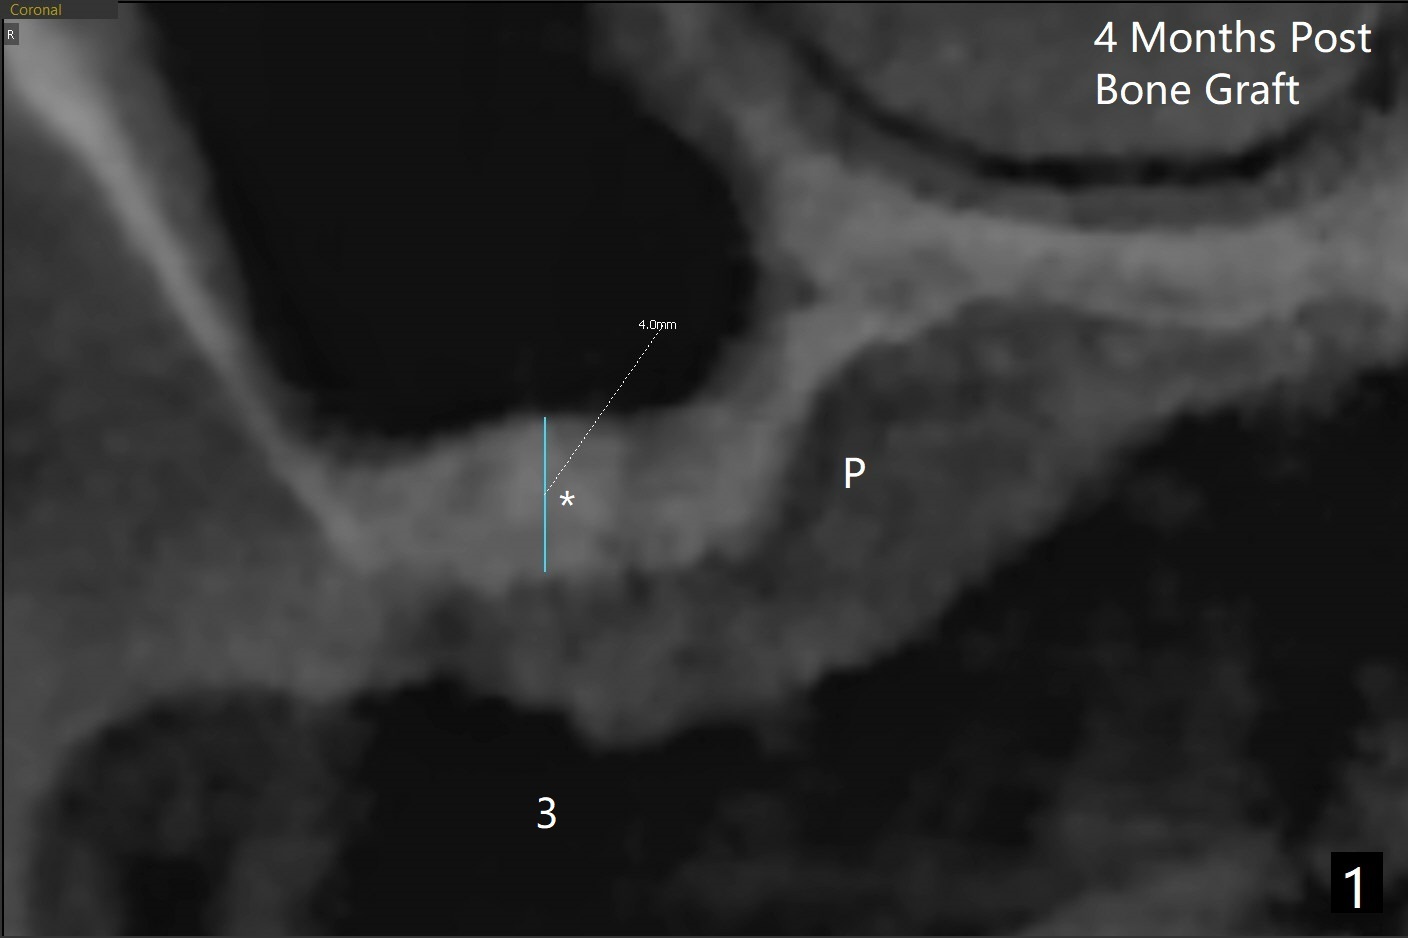

术前清晨复习3号牙窦底,中央是植骨(图一,二:*(皮质骨:密度高,质地可能软)),由于窦底斜坡,术前估计穿孔可能最先发生在远中,术中的确如此(图三:<(使用4毫米钻头后)),放置粘性骨粉(图四),利用导板(图五:G)和4x9毫米报废植体提升(*)。使用4.5毫米钻头,放置半张PRF膜,骨粉,5x7毫米植体以及修复基台,最后在后两者周围放置骨粉(图六,七:*(腭侧一个螺纹暴露)),覆盖1/2PRF膜,缝合,树脂敷料。